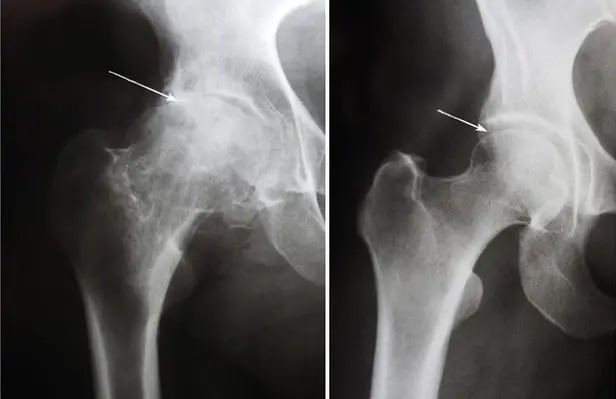

AVANT

APRÈS

rétrécissement de l'espace

articulaire

position correcte des

articulations